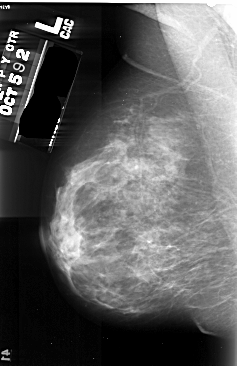

A_1029_1.LEFT_MLO

LEFT_MLO LINES 5476 PIXELS_PER_LINE 3541 BITS_PER_PIXEL 16 RESOLUTION 42 NON_OVERLAY